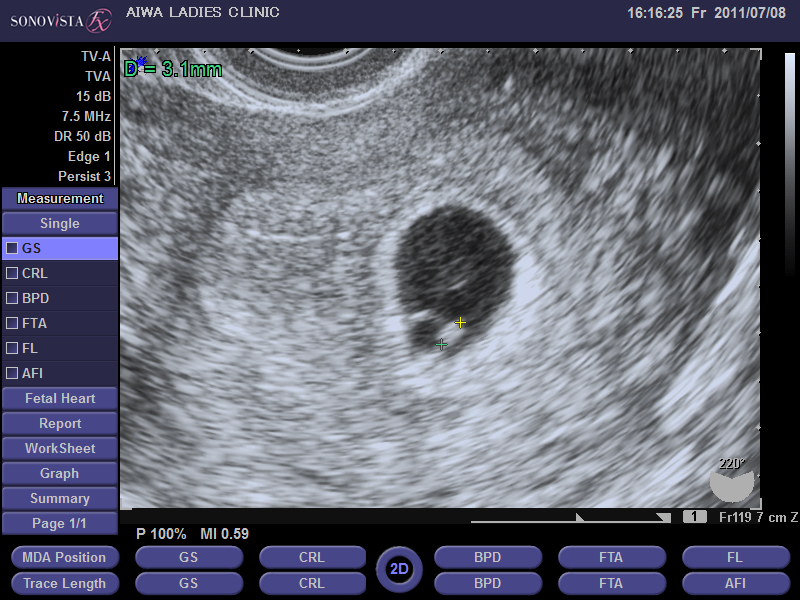

5 産科一般超音波検査 初期編 正常所見4 7週 日本産婦人科医会

5 産科一般超音波検査 初期編 正常所見4 7週 日本産婦人科医会

5 産科一般超音波検査 初期編 正常所見4 7週 日本産婦人科医会

5 産科一般超音波検査 初期編 正常所見4 7週 日本産婦人科医会